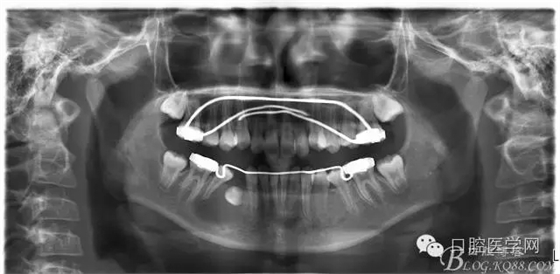

術(shù)后一個月 三個月 五個月 八個月 拔除第一雙尖牙后曲斷片:

正畸查:替牙合。第一恒磨牙中性合。上牙弓尖圓型下牙弓方圓型。前牙覆合3度覆蓋7.5mm。下前牙咬到上舌側(cè)牙齦。上頜擁擠4.0mm,下頜擁擠

3.0mm。上頜稍前突下頜后縮,上下唇前突,上前牙覆蓋下唇,下唇外翻。面下三分之一過短,頦唇溝明顯,開唇露齒,頦饜窩明顯。顳下頜關(guān)節(jié)開閉口無彈響,無壓痛,開口型開口度正常。